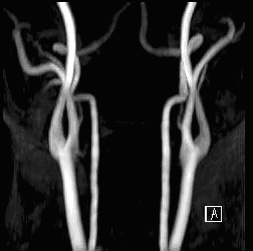

圖二

圖一、圖二由影像醫學科賴彥君醫師提供圖片及解說

這是另外一位受檢者,利用磁振血管造影顯示出大腦內部血管的狀況,主要的大腦血管均暢通,無明顯狹窄的情形。 此外,除了大腦內部的血管可探查清楚之外,雙側的頸動脈血管及更深部的椎動脈亦可在同一次檢查當中一目瞭然 (如上圖所示)